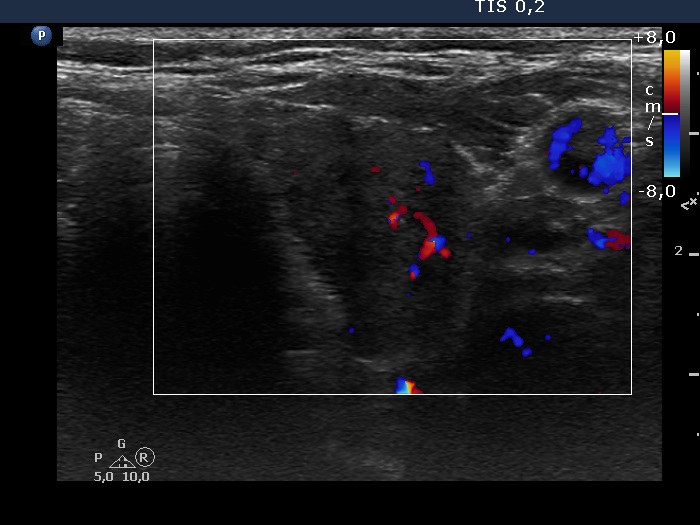

Left lobe, transverse view, color Doppler mode. The vascularization is average.